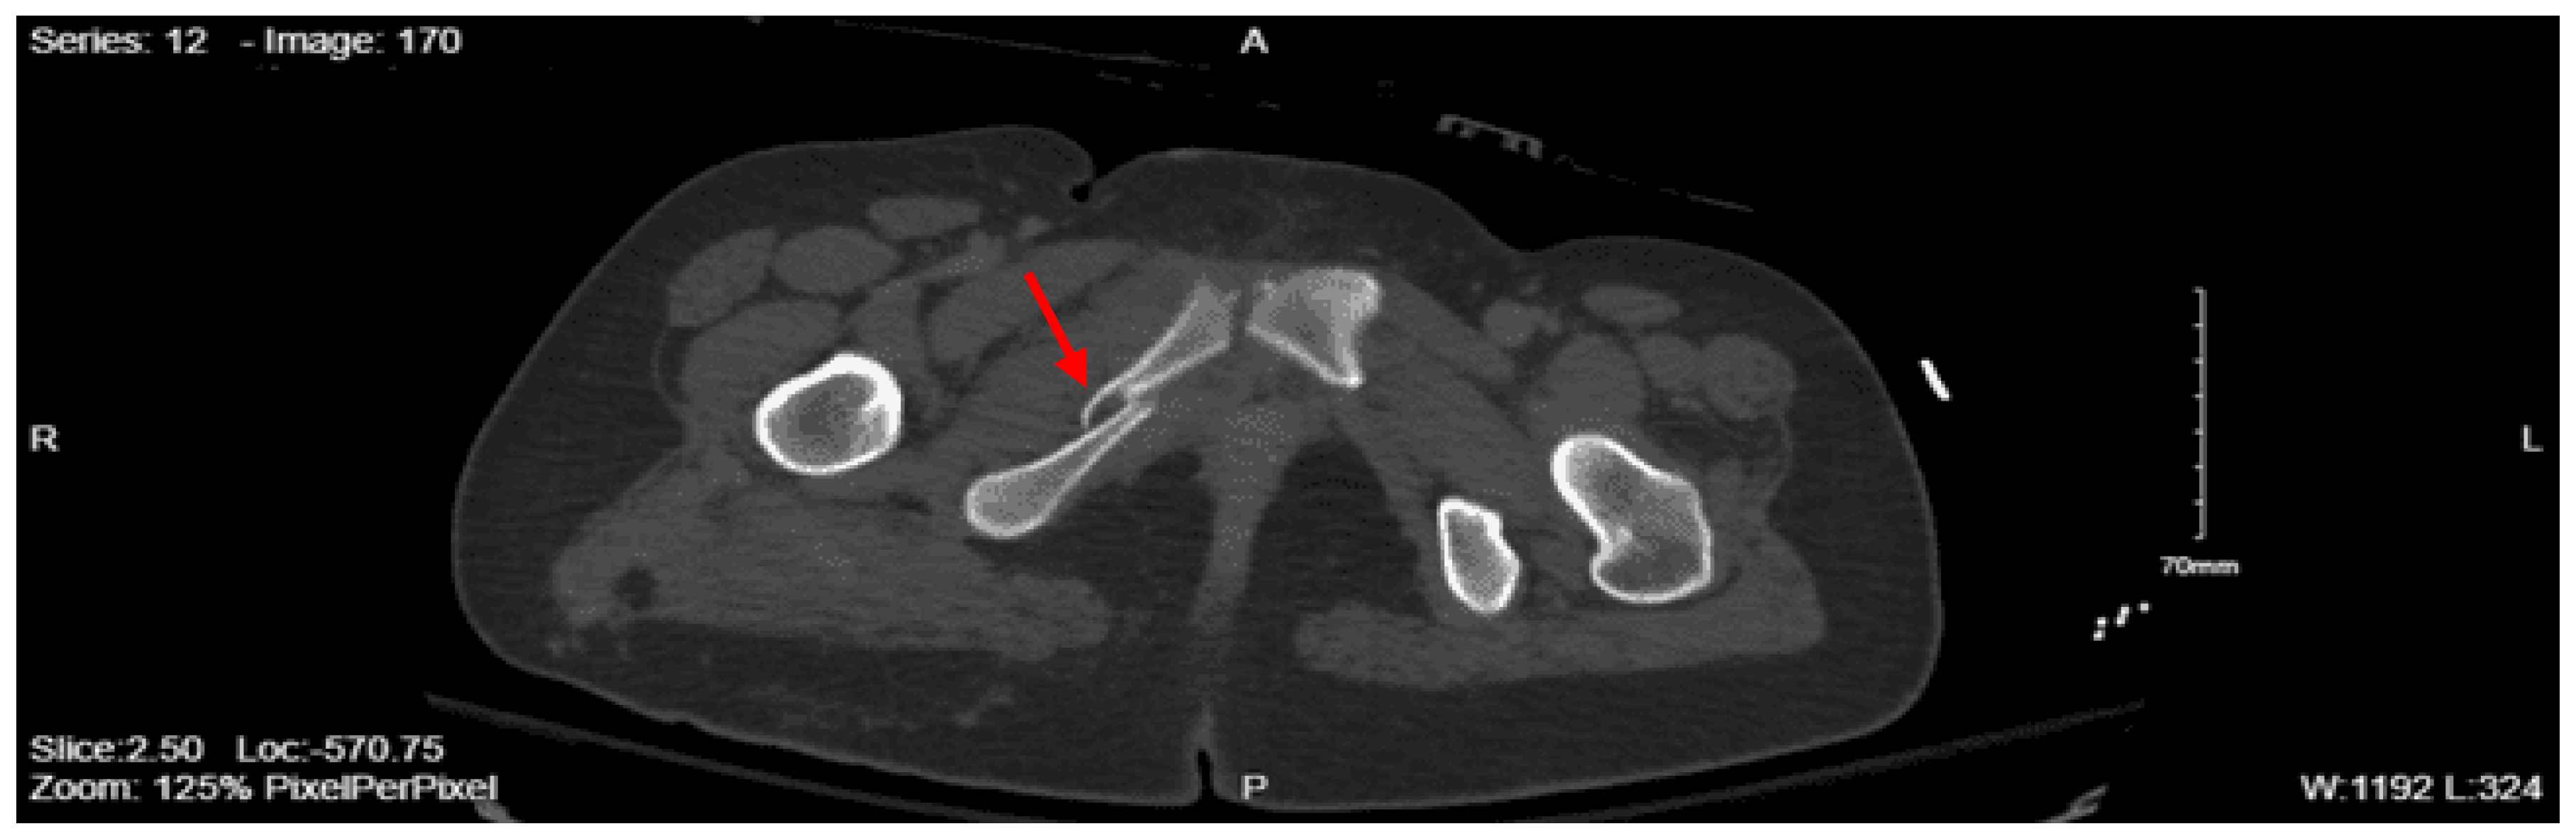

Imaging as shown in Figure 19 and Figure 20:

Portable Pelvic XR: Mildly displaced comminuted subtrochanteric fracture of the right proximal femur

CT Abdomen Pelvic with contrast: No evidence of acute visceral injury. Redemonstration of fractures of the proximal right femur. Fractures of the right inferior petrous and right transverse processes of L2 and L3.

CT femur w/o contrast, Right: Comminuted fracture of the proximal subtrochanteric right femur with posterior medial displacement. Nondisplaced fracture of the right inferior pubic ramus.